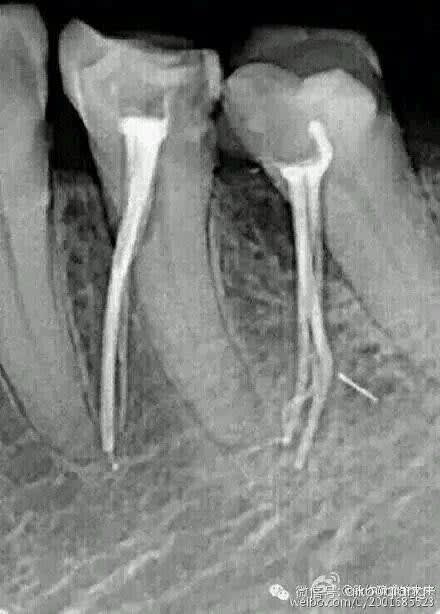

Du grand art :-)

et on remarquera que le mec a non seulement obturé, mais cerise sur le gâteau il a pété une lime...

C'est fort, il a quasiment obturé à l'apex... de la dent adjacente! :-)

le pire en soit c'est pas les perfos (meme si c'est fort), c'est surtout de laisser les cones. Le gars ne doit meme pas faire de radio post op. C'est bien, tant mieux, c'est pas bien, c'est la meme chose

En tout cas il ne fait pas du mono-cône lui. Pour bien faire il en a mis plusieurs jusqu'à l'apex, histoire d'avoir une bonne condensation :-)

Toujours bien analyser une radio pre operatoire que ca soit en endo, en chir ou n'importe quoi

Le praticien a du etre surpris par la mesioversion des dents

Il faudrait surtout qu'il apprenne passer de la fraise diamantée à la zekrya endo une fois dans la chambre pulpaire, à prendre des radio per opératoires lorsque les choses se déroulent "bizarrement", à ouvrir les yeux tout simplement...